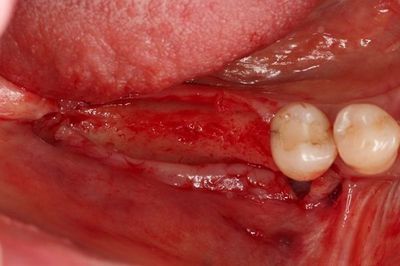

今回は角化歯肉の幅が狭いことと、

抜歯後の年数が経ち骨が完全に治癒していますので埋入トルクが大きく出ることを想定し

1回法(オペ時に粘膜外にインプラント関連構造物を露出させ縫合する方法)となる可能性が高いため

粘膜剥離してからファーストドリリングを行います。

![]()

インプラントの埋入を終えました。

別アングルです。